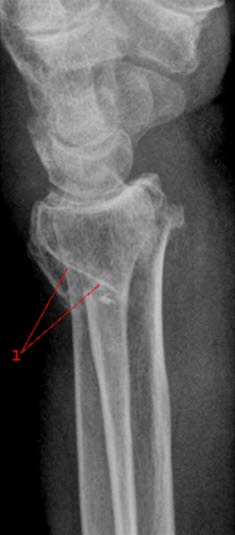

Brudd i nedre del av radius, mindre enn 4 cm fra nedre ende av beinet, betegnes på fagspråket som distalt radiusbrudd eller fractura radii typica. Denne bruddtypen kan medføre at de to bruddendene spriker eller blir forskjøvet i forhold til hverandre, men bruddet kan også være uten forskyvning av bruddendene. I unntakstilfelle kan bruddet skade nerver som ligger nær.

Røntgenbilder tatt forfra og fra siden bekrefter diagnosen (se over). Man ser etter feilstillinger, om det er brudd som innbefatter selve håndleddet, om det er ujevnheter i leddspalten, eller om det foreligger andre beinskader.

Det anbefales operasjon dersom man på røntgenbildene finner tegn til manglende stabilitet i bruddet. Kompliserte brudd som går inn i leddet, eller hvor det er knusning av beinvev, vil alltid bli operert. Den mest brukte operasjonsmetoden er innsetting av en metallplate over bruddspalten. Det er også mulig å stabilisere bruddet med metallpinner som går gjennom huden.